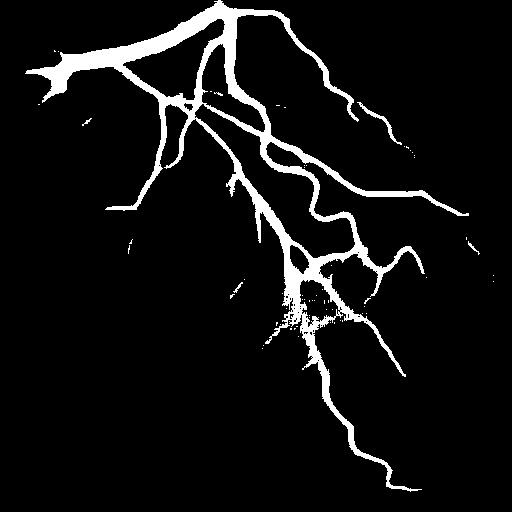

4.1 XACV Dataset

We collect 111 complete records of coronary artery X-ray videos, encompassing the injection, flow through the blood vessels around the heart, and dissipation of the contrast agent. Subsequently, we establish the XACV (X-ray Angiography Coronary Video) dataset. Each video consists of varying numbers of high-resolution coronary artery X-ray images. We invite experienced radiologists to annotate the vascular regions, focusing on one or two frames where the contrast agent is most prominent in each video. The XCAD dataset contains only a single image, and the CADICA video dataset does not provide corresponding ground truth. Therefore, in the following experiments, we conduct all the analyses on our collected XACV dataset and the corresponding GT for each sequence. In Figure 5, we show that compared to other publicly available datasets, XCAD [33] and CADICA [19], our dataset exhibits finer annotations in the vascular regions, providing an advantage for future related tasks. The development and use of our dataset have been approved by our institution’s IRB.